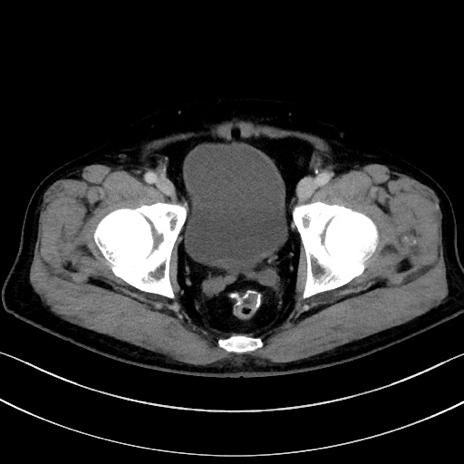

冠状断像

【症例】70歳代男性

【主訴】腹痛

【現病歴】今朝から腹痛あり。全体的に痛い。特に左上の方。排ガスが今日はない。冷や汗が出る。

【既往歴】直腸癌術後

【身体所見】左側腹部〜上腹部に圧痛あり。腹膜刺激症状明らかなではない。軽度反跳痛。左下腹部に術後瘢痕あり。

【データ】WBC 7700、CRP 0.02